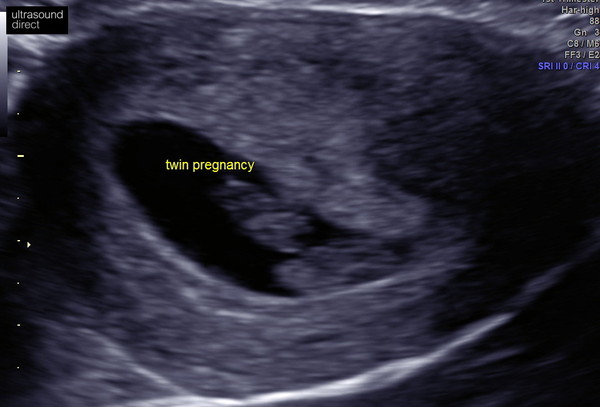

When I went for an early scan they thought my babies were MCMA as they couldn't see a dividing membrane but couldn't say for certain (my first scan pic shows how close they were). When i was scanned at 12weeks the hospital then said they were MCDA as there was a membrane (albeit very thin and sometimes hard to locate).